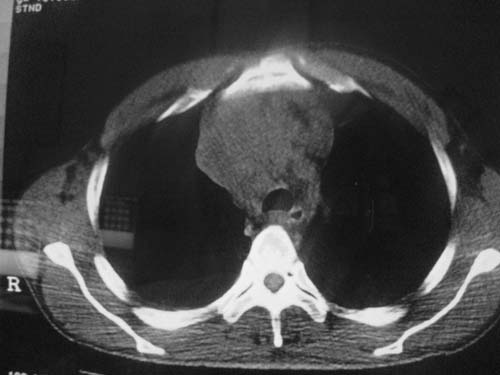

以下是引用科室第一人在2010-3-25 20:30:00的发言:[br]1:纵膈肿瘤性病变,恶性胸腺瘤可能性大伴纵膈右肺门淋巴结转移,右侧胸腔积液。[br]2:右侧肺门肿瘤性病变,纵膈淋巴结转移,右侧胸腔积液。右下叶转移。

以下是引用子期在2010-3-25 21:00:00的发言:[br]先考虑右中央型肺癌伴转移。

以下是引用江广1996在2010-3-25 22:49:00的发言:[br]通常肺癌向纵隔转移多见,纵隔肿瘤向肺内转移少见(有的表现为向肺内侵润)。本例以一元论考虑:右中心型肺癌并纵隔淋巴等多处转移。[br][br][本贴已被 江广1996 于 2010-3-25 22:50:07 修改过]

以下是引用yangyudong333在2010-3-26 6:43:00的发言:[br]“冰冻纵膈”,考虑纵膈淋巴瘤伴肺内及胸膜侵润。